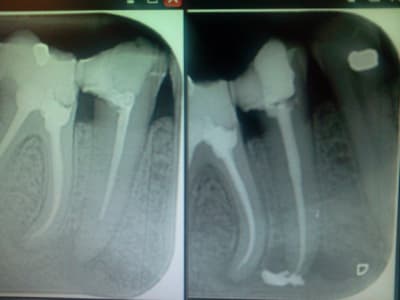

Normalement je fais pas sauf si on me le demande expressement, mais je suis aller montrer ta radio au service d'endo:

1 le produit que tu utilise est une produit de scellement et pas d'obturation canalaire, normalement tu n'es pas senser remplir le canal avec.

2 Il est impossible que tu sois aller dans les vaisseaux sanguin en injectant dans un canal préparé. Pour eux c'est un dépassement classique, la viscosité du produit étant différente de la guta ou ciment classique (le mode d'injection étant différent aussi) ça te donne se look atypique.

Pour les suites ils ne savent pas vue qu'il utilise les sealant pour seller donc ils en mettent très peut.

Probablement pas de problème vue que c'est un produit qui à était élaborés dans l'optique de dépassement canalaire possible.

Plantage il faut pas pousser non plus, il s'agit d'un simple dépassement, l'apparence inhabituelle est due au produit qui n'est pas employer comme matériaux d'obturation habituellement (ne seraisse qu'en raison du prix qui est nettement plus élever que la guta). En aucun cas le matériaux n'a était injecter dans les vaisseaux sanguin.

Normalement il est résorbable (vérifier sur la notice, sinon contacter le fabriquant). Vue la quantité il y a un risque qu'il irrite la patiente mais même ça c'est pas sure.

A priori impressionnant mais moins grave que si il y avait eu un dépassement de guatta avec bris de lentulo dans la racine palatine, (racine inretrétable, en palatin une obturation a retro quasi impossible, l'amputation de racine palatine pas top, avec le dépassement de gutta l'implant on oublie, et possibilité de d'implication sinusienne avec le dépassement)

à l'origine, je ne souhaitais que mettre un peu de ciment de scellement au fond et tapisser la paroi canalaire avec un lentulo pour finir avec la gutta. j'ai poussé un peu trop fort sur la seringue.

pour info, la patiente n'a aucun signe pathologique et se porte bien.

C'est un produit qui normalement a était conçu pour l'éventualité d'un dépassement, en plus il en vendu en seringue donc la composition est parfaitement contrôlée. Vous auriez fait le mélange vous même sus était différent (incident type desmondontite car mélange trop liquide)